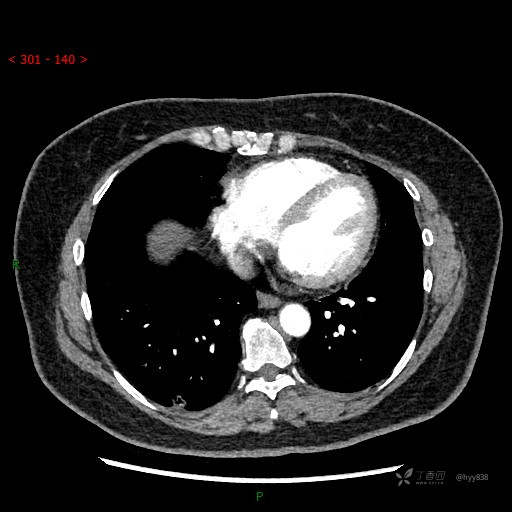

胸部CT增强--动脉期